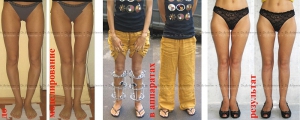

Megjelenése beteg a mini-egységet a sípcsont során a deformáció korrekciója sípcsont

A megjelenése betegek varus deformitás mindkét lábszára használatával mini-bilincs

Az átmenet a gyűrűt a Ilizarov mini rögzítőket célszerűnek 1,5-2 hónappal a műtét után, ha vannak jelei a kialakulását a regenerátumot az osteotomia területen. A műveletek mindkét lábát mini bilincsek lehetővé teszik, hogy lezárja a lábát a térd és értékelje a végleges formája a láb még beállta előtt teljes varrás.